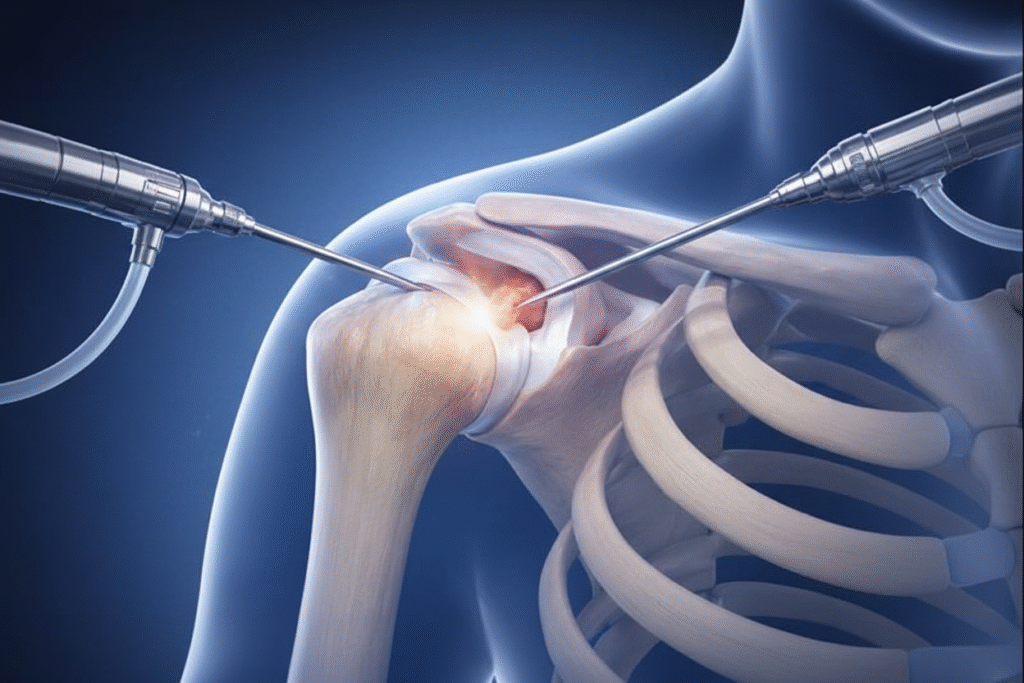

What Is Shoulder Arthroscopy?

Shoulder arthroscopy is a minimally invasive (keyhole) surgical procedure used to diagnose and treat internal problems of the shoulder joint. It allows the best shoulder specialist doctor in Ahmedabad to look inside the joint using a tiny camera and perform repairs through very small incisions.

How Shoulder Arthroscopy is Performed

Small Incisions

Two to three small incisions (about 0.5–1 cm each) are made around the shoulder joint.

Camera Insertion

A thin camera (arthroscope) is inserted through one incision, allowing the surgeon to clearly view the inside of the shoulder on a high-definition monitor

Treatment

Through the other incisions, miniature surgical instruments are used to repair torn tissues, remove bone spurs, or smoothen damaged cartilage

Closure

The small incisions are closed with sutures or adhesive strips, and a sterile dressing is applied.

The entire shoulder arthroscopy procedure typically takes 45–90 minutes, and most patients can return home the same day. This minimally invasive approach ensures less pain, quicker recovery, and early restoration of shoulder movement.